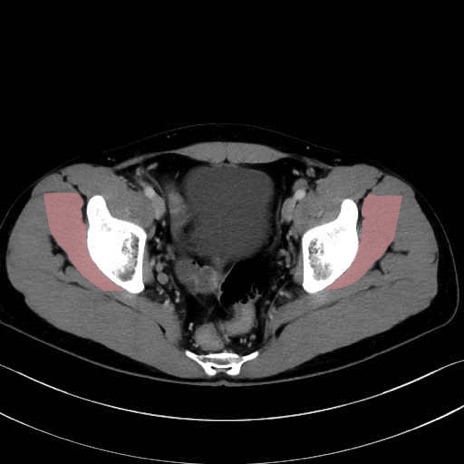

小殿筋 (Gluteus minimus)